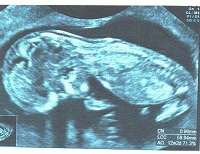

Retard de croissance intra uterinRetard de croissance intra utérin. Lorsqu'un fœtus a une taille insuffisante pour son âge gestationnel, on parle de retard de croissance intra-utérin (RCIU) ou hypotrophie fœtale. Très souvent à l’origine de la prématurité sévère, le retard de croissance intra-utérin, le RCIU, est une pathologie complexe qui concerne plus de 80 000 grossesses par an en France.